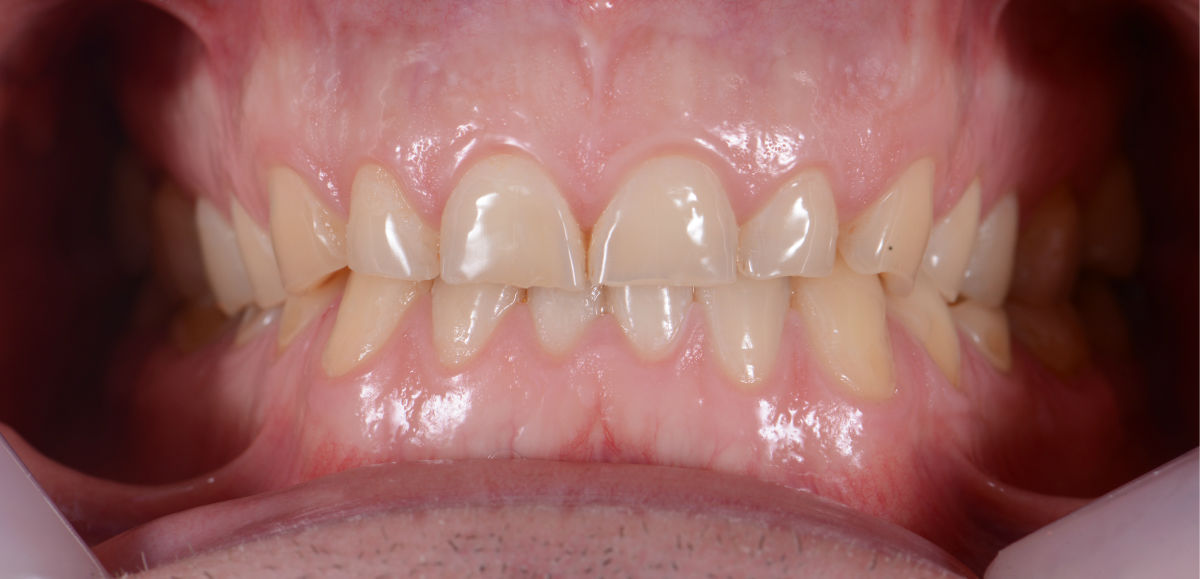

Случай 1: Дигитален дизайн на усмивката в Дента Консулт

Лечение без импланти